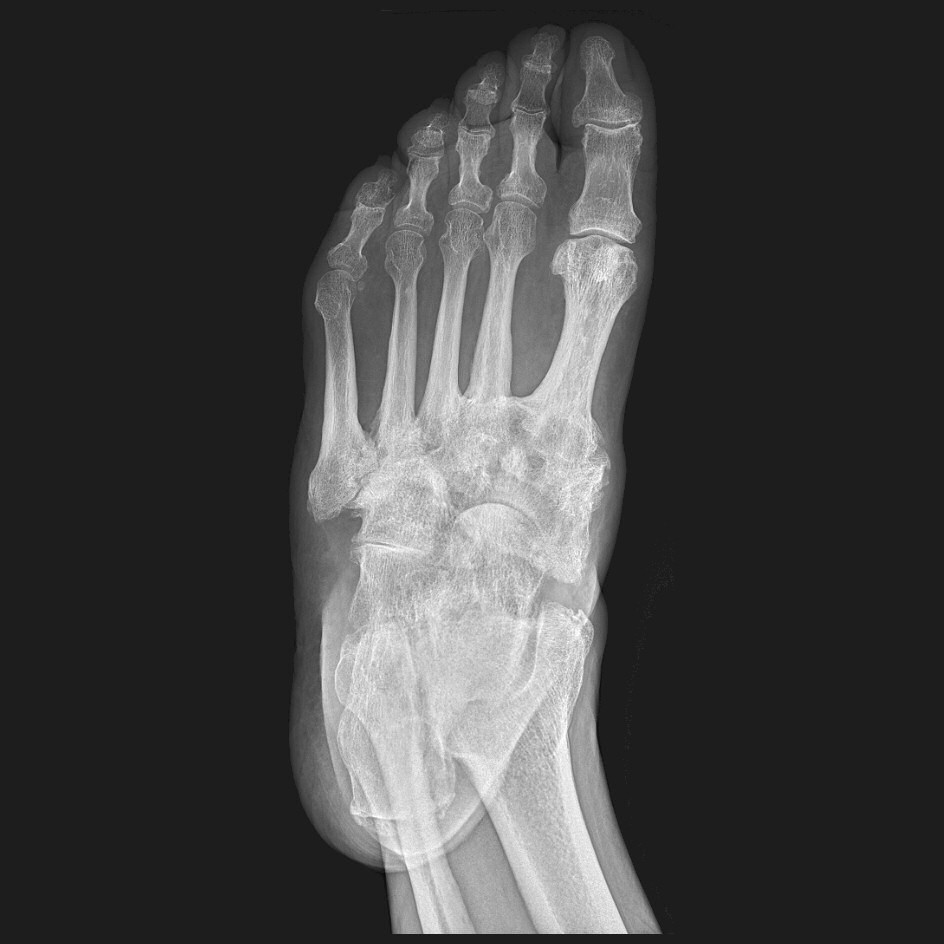

Gammal, läkt charcotfot